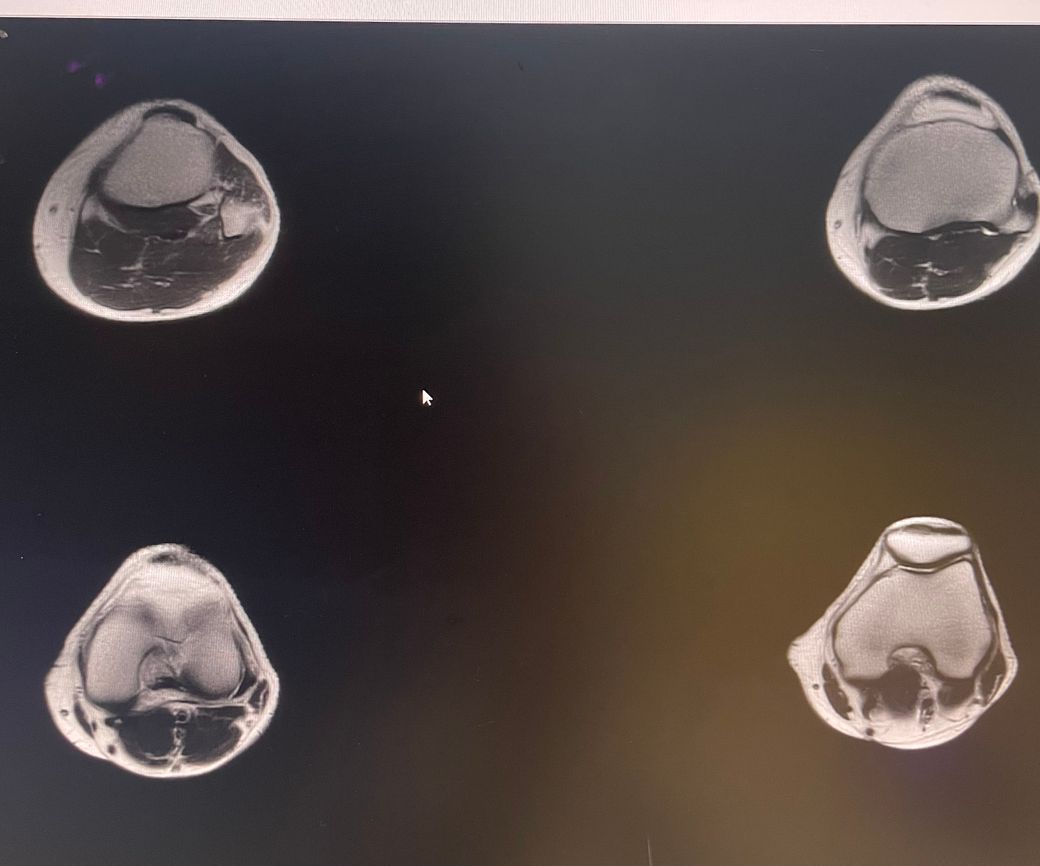

무릎 왼쪽 mri 사진 판독 부탁드리겠습니다.

안녕하세요 3달전쯤에 무릎을 다쳐서 약 한달전에 mri를 찍었습니다.

현재 판독상 인대나 반월연골 손상은 없는 것으로 판독지에 기재되어 있습니다. 임상적인 증상도 중요하니 담당의사와 상의하시고 신검시에 해당과 군의관 판정을 받으시는 것이 좋겠습니다.

십자인대에는 문제가 없지만 반월판의 문제가 있는 것으로 보입니다.

ACL 즉 전방 십자 인대에 불규칙한 소견은 있으나 Tear 즉 십자 인대가 파열되었다는

소견은 관찰되지 않는 상태이며 연골에 퇴행성 변화는 있는 것으로 보이나 이 역시 R/O

으로 확실하지 않음을 의미합니다. 결과적으로 십자 인대의 파열이 명확하지 않는 상태로

군대를 연기할 사유가 될지는 모르며 전방 십자 등 인대 손상의 경우는 명확하게 파열된

소견을 보이지 않는 경우, 군 입대에 문제가 되지는 않을 것으로 생각됩니다.